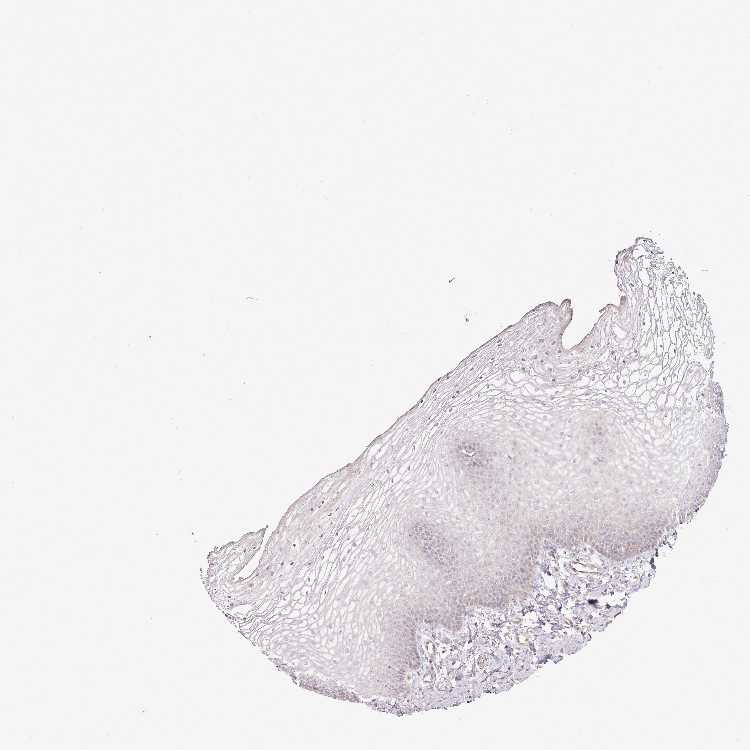

VAGINA - Antibody stainingi

Antibody staining in the annotated cell types in the current human tissue is reported as not detected, low, medium, or high, based on conventional immunohistochemistry profiling in selected tissues. This score is based on the combination of the staining intensity and fraction of stained cells.

Each image is clickable and will lead to virtual microscopy that enables deeper exploration of all samples and also displays staining intensity scores, fraction scores and subcellular localization as well as patient and tissue information for each sample.

Antibody HPA038604Antibody CAB025607

Squamous epithelial cells Not detectedNot detected